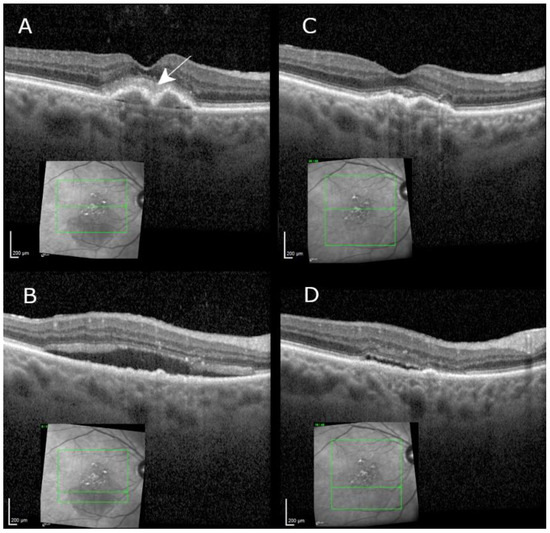

| 84.4 | f | R | 27 | 22 | 6 | 4 weeks after baseline: anterior and intermediate uveitis without vasculitis, 4 weeks after first brolucizumab injection. | |

| 78.1 | m | L | 72 | 41 | 5 | 10 weeks after baseline: panuveitis and retinal occlusive vasculitis 6 weeks after second brolucizumab injection. | |

| 88.8 | f | R | 48 | 10 | 5 | 21 weeks after baseline: adjunctive treatment with intravitreal dexamethasone for persistent intravitreal fluid, 5 weeks after the fifth brolucizumab injection (see text). | |